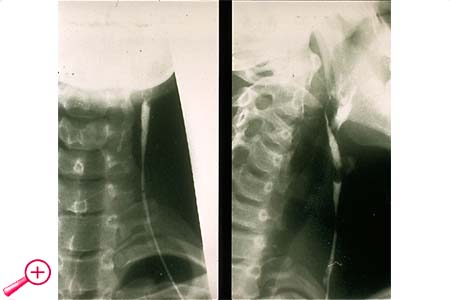

Nach retrograder Injektion eines Kontrastmittels kann ihr Verlauf röntgenologisch dargestellt werden.